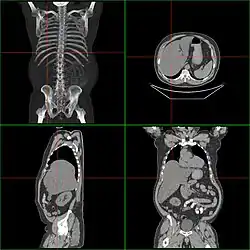

Computerized tomography of affected person with hepatomegaly

Computerized tomography (CT) can give accurate anatomical information for a complete diagnosis.[22]